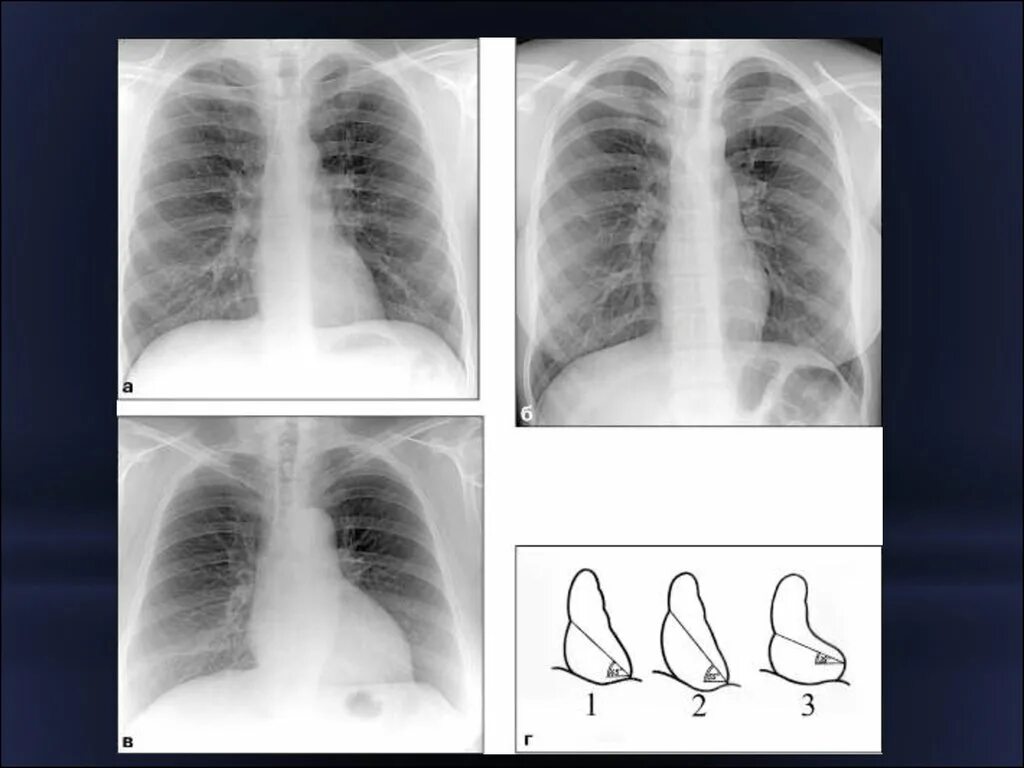

Снимок в прямой проекции